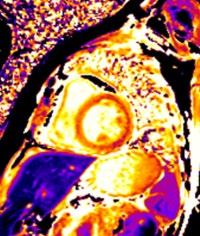

As a result of its unique operating method, photon-counting CT provides several clinical benefits to radiographers. This emerging

technology may improve the ways in which cardiac imaging is performed, increasing spatial resolution in coronary angiography, and reducing radiation noise in cardiac CT imaging. The authors went on to describe the ways in which photon-counting CT may also improve neuroimaging, and tumour detection and imaging, particularly when applied to small tumours and lesions.

"This emerging technology may improve the ways in which cardiac imaging is performed."

The study concluded that photon-counting CT has the potential to surpass conventional CT, as it provides improved spatial resolution, noise elimination, and efficient dose usage. PCD additionally may benefit larger patients, as it addresses artifacts like calcium blooming. Photon-counting CT has a wide range of applications in various areas of medicine, and therefore provides a promising future for radiography. ●